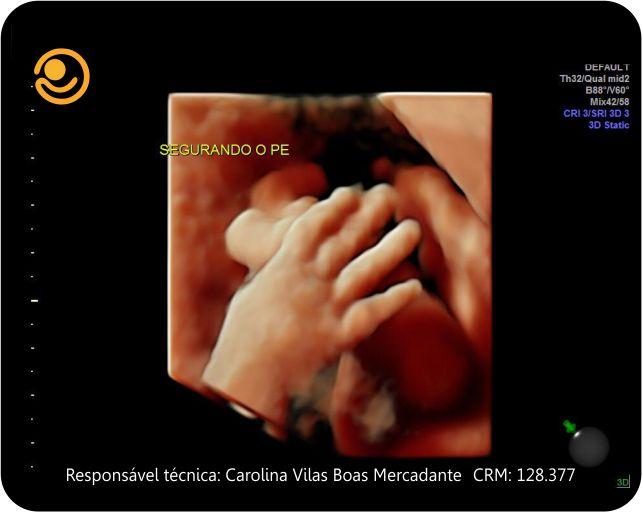

Imagens 3D / 4D

✓ Ultrassonografia 3D/ 4D com imagem em HD